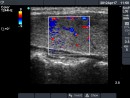

Follow-up examinations (rows from 1st to 8th):

2. Note the relation between volume, echogenicity, vascularization and hormone levels.